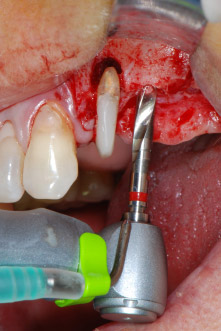

However, we maintained our initial plan to retain both teeth as temporary bridge abutments during the six-months osseointegration period of the implants. At reentry, the situation would have to be reassessed. First, in an attempt to manage the endo-perio problem, the remaining root surface was carefully debrided with piezoelectric equipment (Piezomed, W&H, used with the spatula-shaped insert S1, originally designed for erosion of the lateral sinus wall) (Fig. 4).

Then the apex was abraded with the same instrument to remove residual infected apical tissue and to reduce possible accessory root-canal ramifications (apicoectomy) (Fig. 5). A retrograde filling was not necessary because the orthograde filling had just been revised.